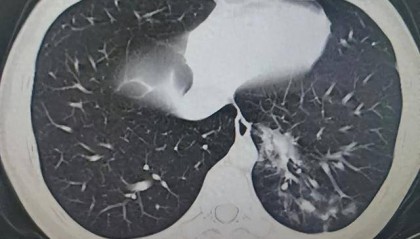

14岁男生4天高烧不退!一查不是甲流,竟是这种感染